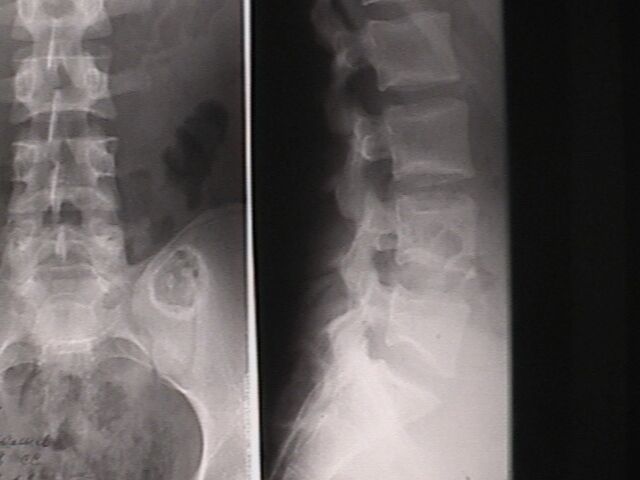

У сына ( 18 лет) медицинской сестры, во время обследования в военкомате на рентгенограмме выявлена опухолевидное образование, клинически бессимптомное.

Больной консультирован в Новосибирском онкологическом диспансере, областной консультативной поликлинике. Поставлен диагнозэнхондрома левой подвздошной кости. Рекомендовано наблюдение контрольное рентгенологическое обследование через год. По-моему лучше бы опухоль назвать экхондромой (рост преимущественный вне кости). Считаю, что лучше предложить оперативное лечение- удаление опухоли Прошу коллег высказать свое мнение. Если необходимо оперативное лечение - где можно его осуществить.

Опухоль выглядит очень продолжительной, хорошо инкапсулированной. Думаю, решение Н-Сиб. онкологов умно и резонно. Если клинически это образование не проявляется и через 1,5-1 год не растет и не перерождаетсято лучше его не трогать. Вы ведь знаете ,что вылущивание опухоли в этом районе не просто, есть возможность конфликта с Sacro-Ileac Joint и с пояс.-крестц. нерв. сплетением. Бессимптомным из этой операции молодой парень, на мой взгляд, не выйдет. И всего хуже, Вам ведь известно, после удаления остатки опухоли (всегда есть остатки!) часто малигнизируют. Мой совет звучит лучше по-украински: не чапай беды.

Посмотрели с коллегой из ортопедического отделения, где как раз доброкачественными опухолями скелета занимаются. Желательно бы

дообследовать пациента - уточнить на КТ форму, размеры и локализацию, показать опытным рентгенологам. Как-то странновато образование

пересекает крестцово-подвздошный сустав.